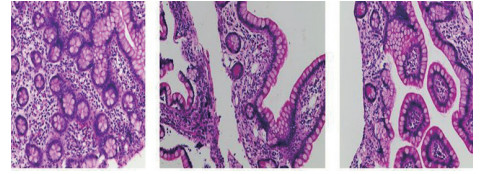

| 图 2 电子结肠镜病理(2017-12-19):示大量嗜伊红细胞,胞质丰富,核深染,细胞表面可见粉红色嗜酸颗粒 |

1 资料与方法患者男,30岁,因“腹胀、腹痛6 d,高热1 d”于2017年12月11日由广州南沙区中心医院转诊收入中山大学孙逸仙纪念医院全科医学科。患者本次起病前无明确病因或明显诱因。患者以左上腹轻微胀痛起病,进行性加重。南沙区医院查血常规:白细胞14.27×109/L,血小板50×109/L,中性粒细胞比例74.5%,嗜酸粒细胞1.02×109/L,嗜酸粒细胞比例7.2%。全腹CT+CTA提示:门静脉左右主干及其小分支栓子形成。后在3 d内连续复查血常规,提示血小板进行性下降,由50×109/L相继降至35×109/L、18×109/L;(嗜酸粒细胞计数及比例未能提供),并出现高热(体温39.5℃),因病情危重,遂转诊本院。入院时患者精神疲乏、高热,腹部胀痛难忍,伴有咳嗽。查体:体温38.6℃,心率87次/min,血压102/76 mmHg,指尖血氧饱和度90%~91%。双肺呼吸音粗,双肺均可闻及小水泡音。腹部稍膨隆,叩诊鼓音,左上腹及脐周轻压痛,无反跳痛。听诊肠鸣音减弱,约1~2次/min。当天查血常规示白细胞11.85×109/L,血小板23×109/L,中性粒细胞比例58.1%,嗜酸粒细胞3.5×109/L,嗜酸粒细胞比例29.5%。凝血常规提示:PT 15.9S,PTA 51.1%,PT/R 1.39,Fbg 1.59 g/L,PTINR 1.39,APTT 35.2 s,D-二聚体114.36 mg/L FEU(参考值范围0~0.55 mg/L FEU)。胸部+全腹部CT+CTA示“门静脉主干及左、右支、肠系膜上静脉近端栓子形成;腹主动脉及左侧髂总动脉小附壁血栓;左肺上叶尖后段、左肺上叶下舌段、右肺中叶及双肺下叶炎症;乙状结肠两段节段性管壁增厚,建议排外占位性病变;腹水、盆腔积液,大网膜炎性病变可能性大”。每日复查血常规,发现血小板进行性下降,最低至15×109/L(参考值范围125~350×109/L),嗜酸粒细胞计数及比例进行性升高,分别达到8.07×109/L(参考值范围0.020~0.52×109/L)和51.1%(参考值范围0.4-8.0%)。每日复查凝血常规亦提示凝血指标不断恶化,纤维蛋白原最低降至0.63 g/L。在予禁食、“美平(美罗培南)”抗感染、输注纤维蛋白原及血小板、维护水电解质平衡及营养支持的积极治疗的同时,还积极完善了以下检查寻找病因:①血液系统方面:血浆鱼精蛋白副凝实验:阳性(+);凝血功能实验:PT 15.5S↑,PTA 47.8%↓,PT/R 1.35↑,PTINR 1.36↑,APTT 40.4 s↑,AT-Ⅲ 57.7%↓,F-VII 32.8%↓,F-Ⅷ 68.1%↓,F-X 68.0%↓,F-XII 24.0%↓;纤维蛋白降解产物:381.4 mg/L↑;血栓弹力-血小板图:R时间10.3 min↑;角度18.5度↓;最大血块强度13.2 mm↓;MA(ADP)值5.6 mm↓。骨髓病理学:嗜酸性粒细胞增多(43%),巨核细胞减少(7个)。慢淋/淋巴瘤表型分析:获取和分析细胞数5.0万;粒细胞区百分比82.6%;淋巴细胞区百分比9.4%;单核细胞区百分比2.0%;CD45dim细胞区百分比1.3%;有核红及细胞碎片区域百分比4.6%。ETV6/PDGFRB融合基因、FIP1L1/PDGFRA融合基因(—)。骨髓细胞学病理结果:符合嗜酸细胞增多症;②消化系统检查:大便细菌培养鉴定及药敏提示无志贺、沙门菌生长,有真菌生长;大便难辨梭菌毒素检测(—);粪便找寄生虫、找阿米巴、寄生虫七项均为(—);消化肿瘤系列提示CA-125 244.8 U/mL↑;腹腔穿刺术穿出“血性腹水”,腹水CA-125 1006.0 U/mL↑,腹水找癌细胞(—);复查腹部CT+CTA:乙状结肠两段节段性管壁增厚,建议进一步检查;排外占位性病变;遂行PET-CT:提示全身未见明确恶性征象。行电子结肠镜示:内镜诊断:(1)回肠末段炎症;(2)乙状结肠炎症;(3)内痔。钳取组织送病理,提示:标本①(回肠末端)黏膜组织呈慢性炎,伴糜烂,一些嗜酸性粒细胞浸润(约35个/HPF);②(乙状结肠)黏膜组织呈慢性炎,伴糜烂,个别嗜酸性粒细胞浸润(约4个/HPF)。③风湿免疫系统方面:免疫八项、风湿四项:C反应蛋134.0 mg/L,余未见异常;总IgE 170 IU/mL↑;抗ENA抗体、狼疮两项、血管炎两项、免疫球蛋白G4、抗心磷脂抗体三项均为阴性;④其他感染病原学检查:乙肝、肝炎系列、性病三项、痰找抗酸杆菌、T-spot实验、流行性出血热、登革热抗体、登革热病毒NS1抗原、外斐氏试验、肥达氏试验、痰结核培养、骨髓培养、血液细菌、血液厌氧菌培养均为阴性。经过上述检查,初步考虑“特发性嗜酸性细胞增多症”,于12.15开始予“甲泼尼松龙40 mg静滴, 1次/d”及“低分子肝素0.6 ml皮下注射, 1次/d”抗炎抗凝治疗。患者病情及检验指标有所好转,热退、腹胀减轻,血常规提示血小板升至49 ×109/L,嗜酸粒细胞计数和比例均下降至正常,凝血常规提示D-二聚体降至47.90 mg/L FEU。但12-22患者自行进食多量米饭后突发腹胀痛较前加重,急查血常规提示白细胞升至21×109/L,血小板再次下降至15×109/L,D-二聚体升至97.28 mg/L FEU,全腹CTA提示“门静脉主干及左、右支、肠系膜上静脉近端新发栓子形成”,遂于当日转至ICU予“尿激酶20万U+肝素钠1250 U”溶栓治疗后予“低分子肝素0.6 ml皮下注射, 1次/12 h”序贯抗凝治疗。后患者病情渐渐稳定,至2018-1-18患者在“甲泼尼松龙12 mg口服, 1次/d”及“立伐沙班20 mg口服, 1次/d”的维持治疗下,血小板、嗜酸粒细胞计数及纤维蛋白原均回复正常,D-二聚体下降至3.52 mg/L FEU。但遗憾的是,此时患者再次进食大量米饭,约1 h后突发腹痛、气促,急行胸片+腹平片提示:“双侧膈下游离气体,考虑胃肠道穿孔可能;双下肺少许炎症,少量胸腔积液;腹部多量积气伴肠腔扩张”。遂即送手术室行全麻下“腹腔镜探查+坏死空肠切除+大网膜切除+肠系膜上动脉探查+空回肠双腔造口术”,术后病理提示标本①(大网膜)脂肪组织,部分坏死,合并慢性炎,伴一些中性粒细胞浸润,较多泡沫样组织增生,未见明确血栓,未见恶性改变。②(部分空肠)肠壁组织,部分肠壁全层坏死,合并慢性炎,肉芽组织增生,未见明确血栓,未见恶性改变。免疫组织化学:CD38浆细胞(+)、IgG(+)、IgG4(﹣)。术后继续予“立伐沙班10 mg/d”和“甲泼尼松龙8 mg/d”口服治疗,并于2018.2.4停用“甲泼尼松龙”。2.28复查全腹CTA,仍可见“脾静脉新发血栓,门静脉及肠系膜上静脉血栓较前好转”。3.20行空回肠双腔造瘘管泛影葡胺造影术提示“双腔造瘘管通畅,右中下腹小肠蠕动尚可,结肠各段及直肠通畅,未见对比剂外漏征象”。但患者合并了严重的短肠综合征,致严重低钾低钠血症和继发的代谢性脑病,病情再度转危。继续纠正电解质紊乱、补充营养,最终病情好转后于4.11行“造瘘口回纳修补术”。随访半年,患者仍口服“立伐沙班10 mg/d”抗凝治疗,复查血常规、凝血常规等各项指标均正常,但营养状况较差。